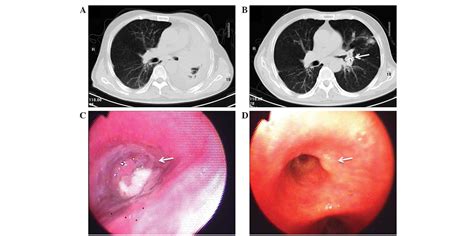

• CT Scan: A more detailed imaging test that provides a clearer picture of the lung tissue and any potential tumors.

• Bronchoscopy: A procedure where a flexible tube with a camera is inserted into the lungs to visualize the airways and collect tissue samples.